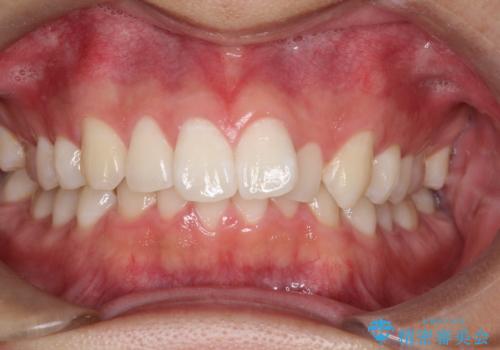

正面から見たときに右上2が全く見えないくらい、右上2が後ろに引っ込んでいる状態でしたが綺麗に並べる事が出来ました。

笑った時のスマイルラインもかなり綺麗になり大変ご満足いただく事が出来ました。

スムーズに治療を進める事ができ、2年2か月で治療をお終えました。

顔貌に対して歯の正中も合いました。